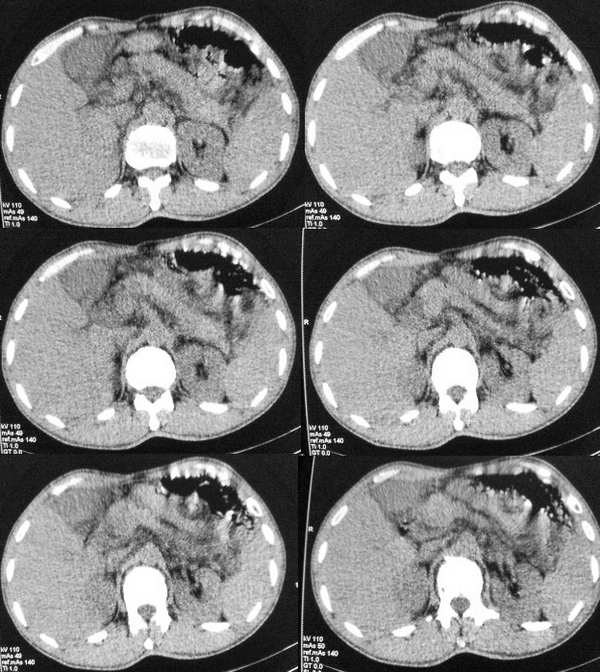

以下是引用butterylf在2005-12-21 19:10:00的发言:[br]我扫出来的图像都是这样的,窗宽窗位我参考了别的医院的啊,可是为什么我扫出来的图像质量不好,不好意思,是从显示器上拍的,而且还是用手机拍的,我不知道其他还能有什么方法拍啊!![br]病人是男性,41岁,[br]另外mas怎么调,不是不同的部位都要重新调过吧,?[br][br][br]对了,各位老师,我想问一个问题,我现在扫描片子打不出来了,这是为什么?ct已经传送过去了,可是激光打印就是出不来啊,打印机上总是显示close lower cover?这是为什么啊?